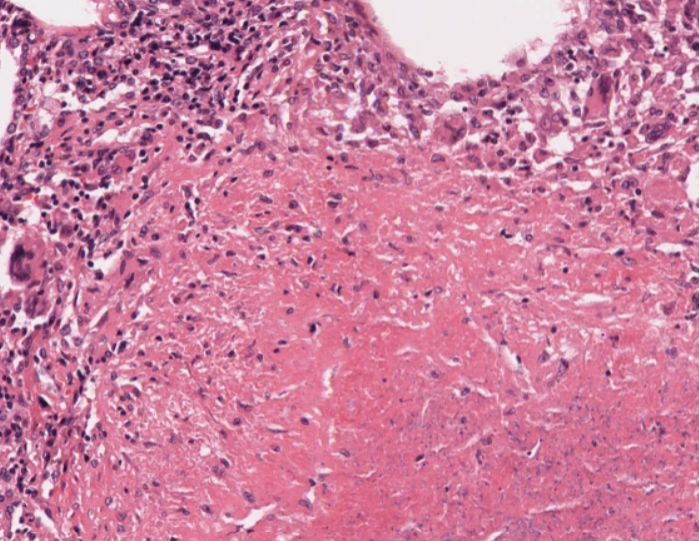

#caseoftheweek 🔬🔬🔬 What is causing this vulval lesion in this 57 year old woman? View the full slides on the Leeds Virtual pathology website here: virtualpathology.leeds.ac.uk/slides/library… #pathX #PathTwitter #gynaepath